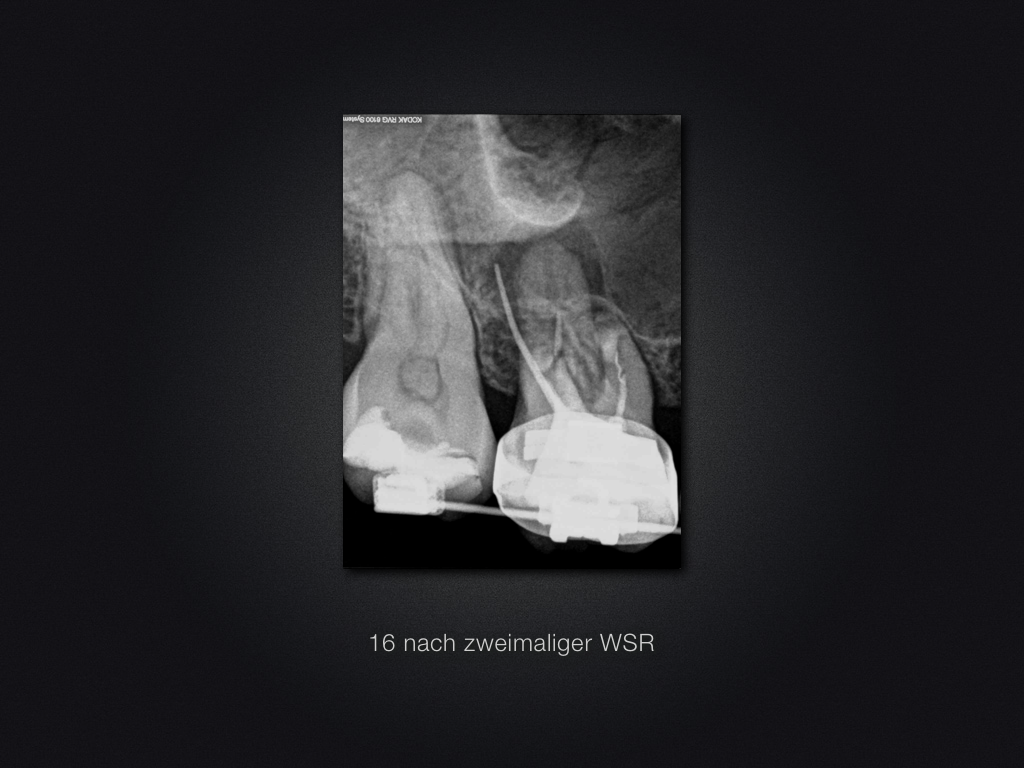

Saving Hopeless Teeth (XXXIII)